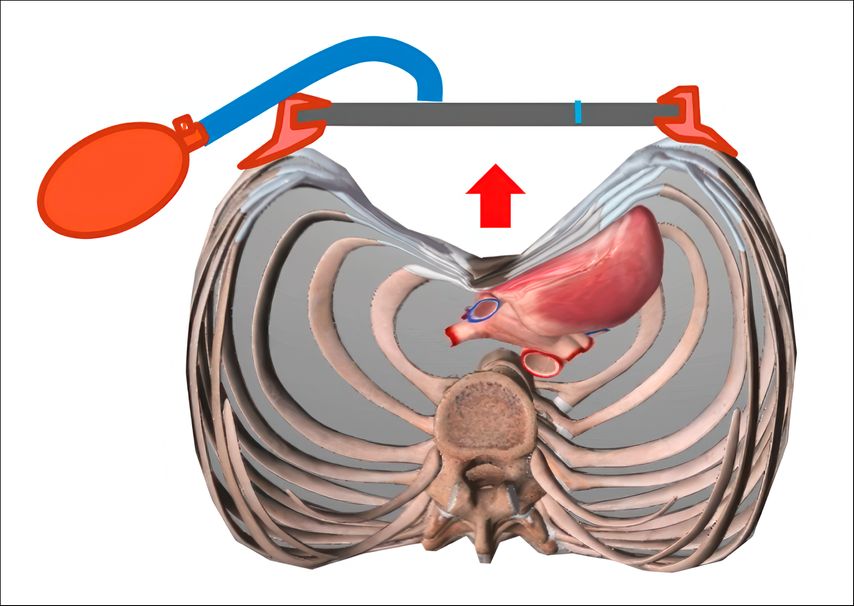

Zur physikalisch-konservativen Behandlung gehört der Einsatz einer thorakalen Saugglocke (Abb.3). Es sollte für diese Behandlung ein flexibler Thorax mit sonografisch erkennbarer elastischer Manubrium-Korpus-Zone des Brustbeins vorliegen. Die größten und rasch korrigierenden, ggf. gänzlich kurativen Erfolge können gerade bei jungen Trichterbrustpatienten erzielt werden.14–17 Die Therapien können in kooperativen Behandlungssituationen bereits im Volksschulalter stattfinden, in jedem Fall aber im Zuge des pubertären Wachstumsschubes. Die Unterdrucktherapie mittels Saugglocke steigert die sportliche Leistungsfähigkeit (CO) und flexibilisiert in jedem Fall den Thorax. Dadurch fällt bei einer doch notwendig erscheinenden späteren Operation zur Totalkorrektur die postoperative Schmerzproblematik geringer aus, nachdem der Brustkorb an den passager während der Heilbehandlung nahezu ausgeglichenen Trichter vorweg adaptiert ist.

Für die spezielle Situation, in der vorgewölbte untere Rippenbögen („flared ribs“) vorhanden sind, bewährt sich als aktuelle innovative Entwicklung die Y-förmig gestaltete Unterdruck-Überdruck-Saugglocke® (Abb.4), die einerseits den Trichter abflacht, gleichzeitig aber auch eine Kompression auf vorspringende untere Rippenbögen (Abb.5) ausübt und die komplette Umformung provoziert. Alle Saugsysteme machen den Brustkorb grundsätzlich beweglicher.

Die konservative Saugglocken-Behandlung sollte täglich (ca.2h) Anwendung finden und hat die besten Ergebnisse bei jungen Patienten, bei denen die Therapie bereits im Alter von 10 Jahren begonnen wurde. Schon eine Therapiepause von 3 Tagen kann zu einem Rückfall führen infolge des sogenannten „Gewebe-Memorys“, das erst nach zumindest dreimonatiger Behandlung schrittweise abnimmt. Auch wenn in bestimmten Fällen eine operative Totalkorrektur notwendig erscheint, hat sich die Saugglocken-Flexibilisierung des Thorax als vorteilhaft erwiesen.